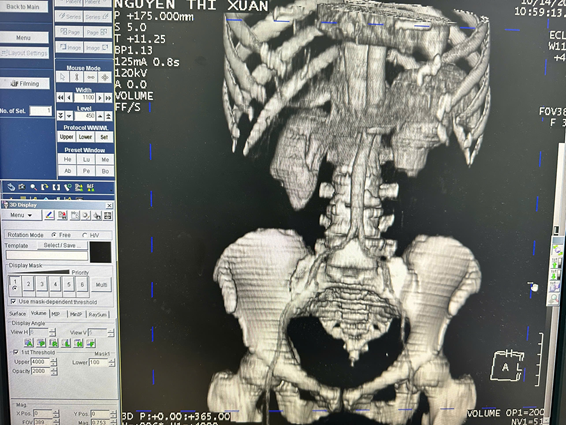

Chụp CT Scan là kỹ thuật sử dụng tia X kết hợp với máy tính hiện đại để tạo ra hình ảnh cắt lớp chi tiết, sắc nét, giúp quan sát rõ các cấu trúc bên trong cơ thể. Khi được tiêm thuốc cản quang, hình ảnh thu được càng rõ nét hơn, giúp làm nổi bật mô mềm, mạch máu và cơ quan nội tạng, từ đó hỗ trợ bác sĩ phát hiện và đánh giá chính xác các tổn thương. Kỹ thuật này cho phép hiển thị hình ảnh theo nhiều mặt cắt khác nhau như: ngang, dọc và đứng, giúp bác sĩ có cái nhìn toàn diện về vùng cần khảo sát.

- Đánh giá chấn thương vùng đầu, ngực, bụng, xương khớp.